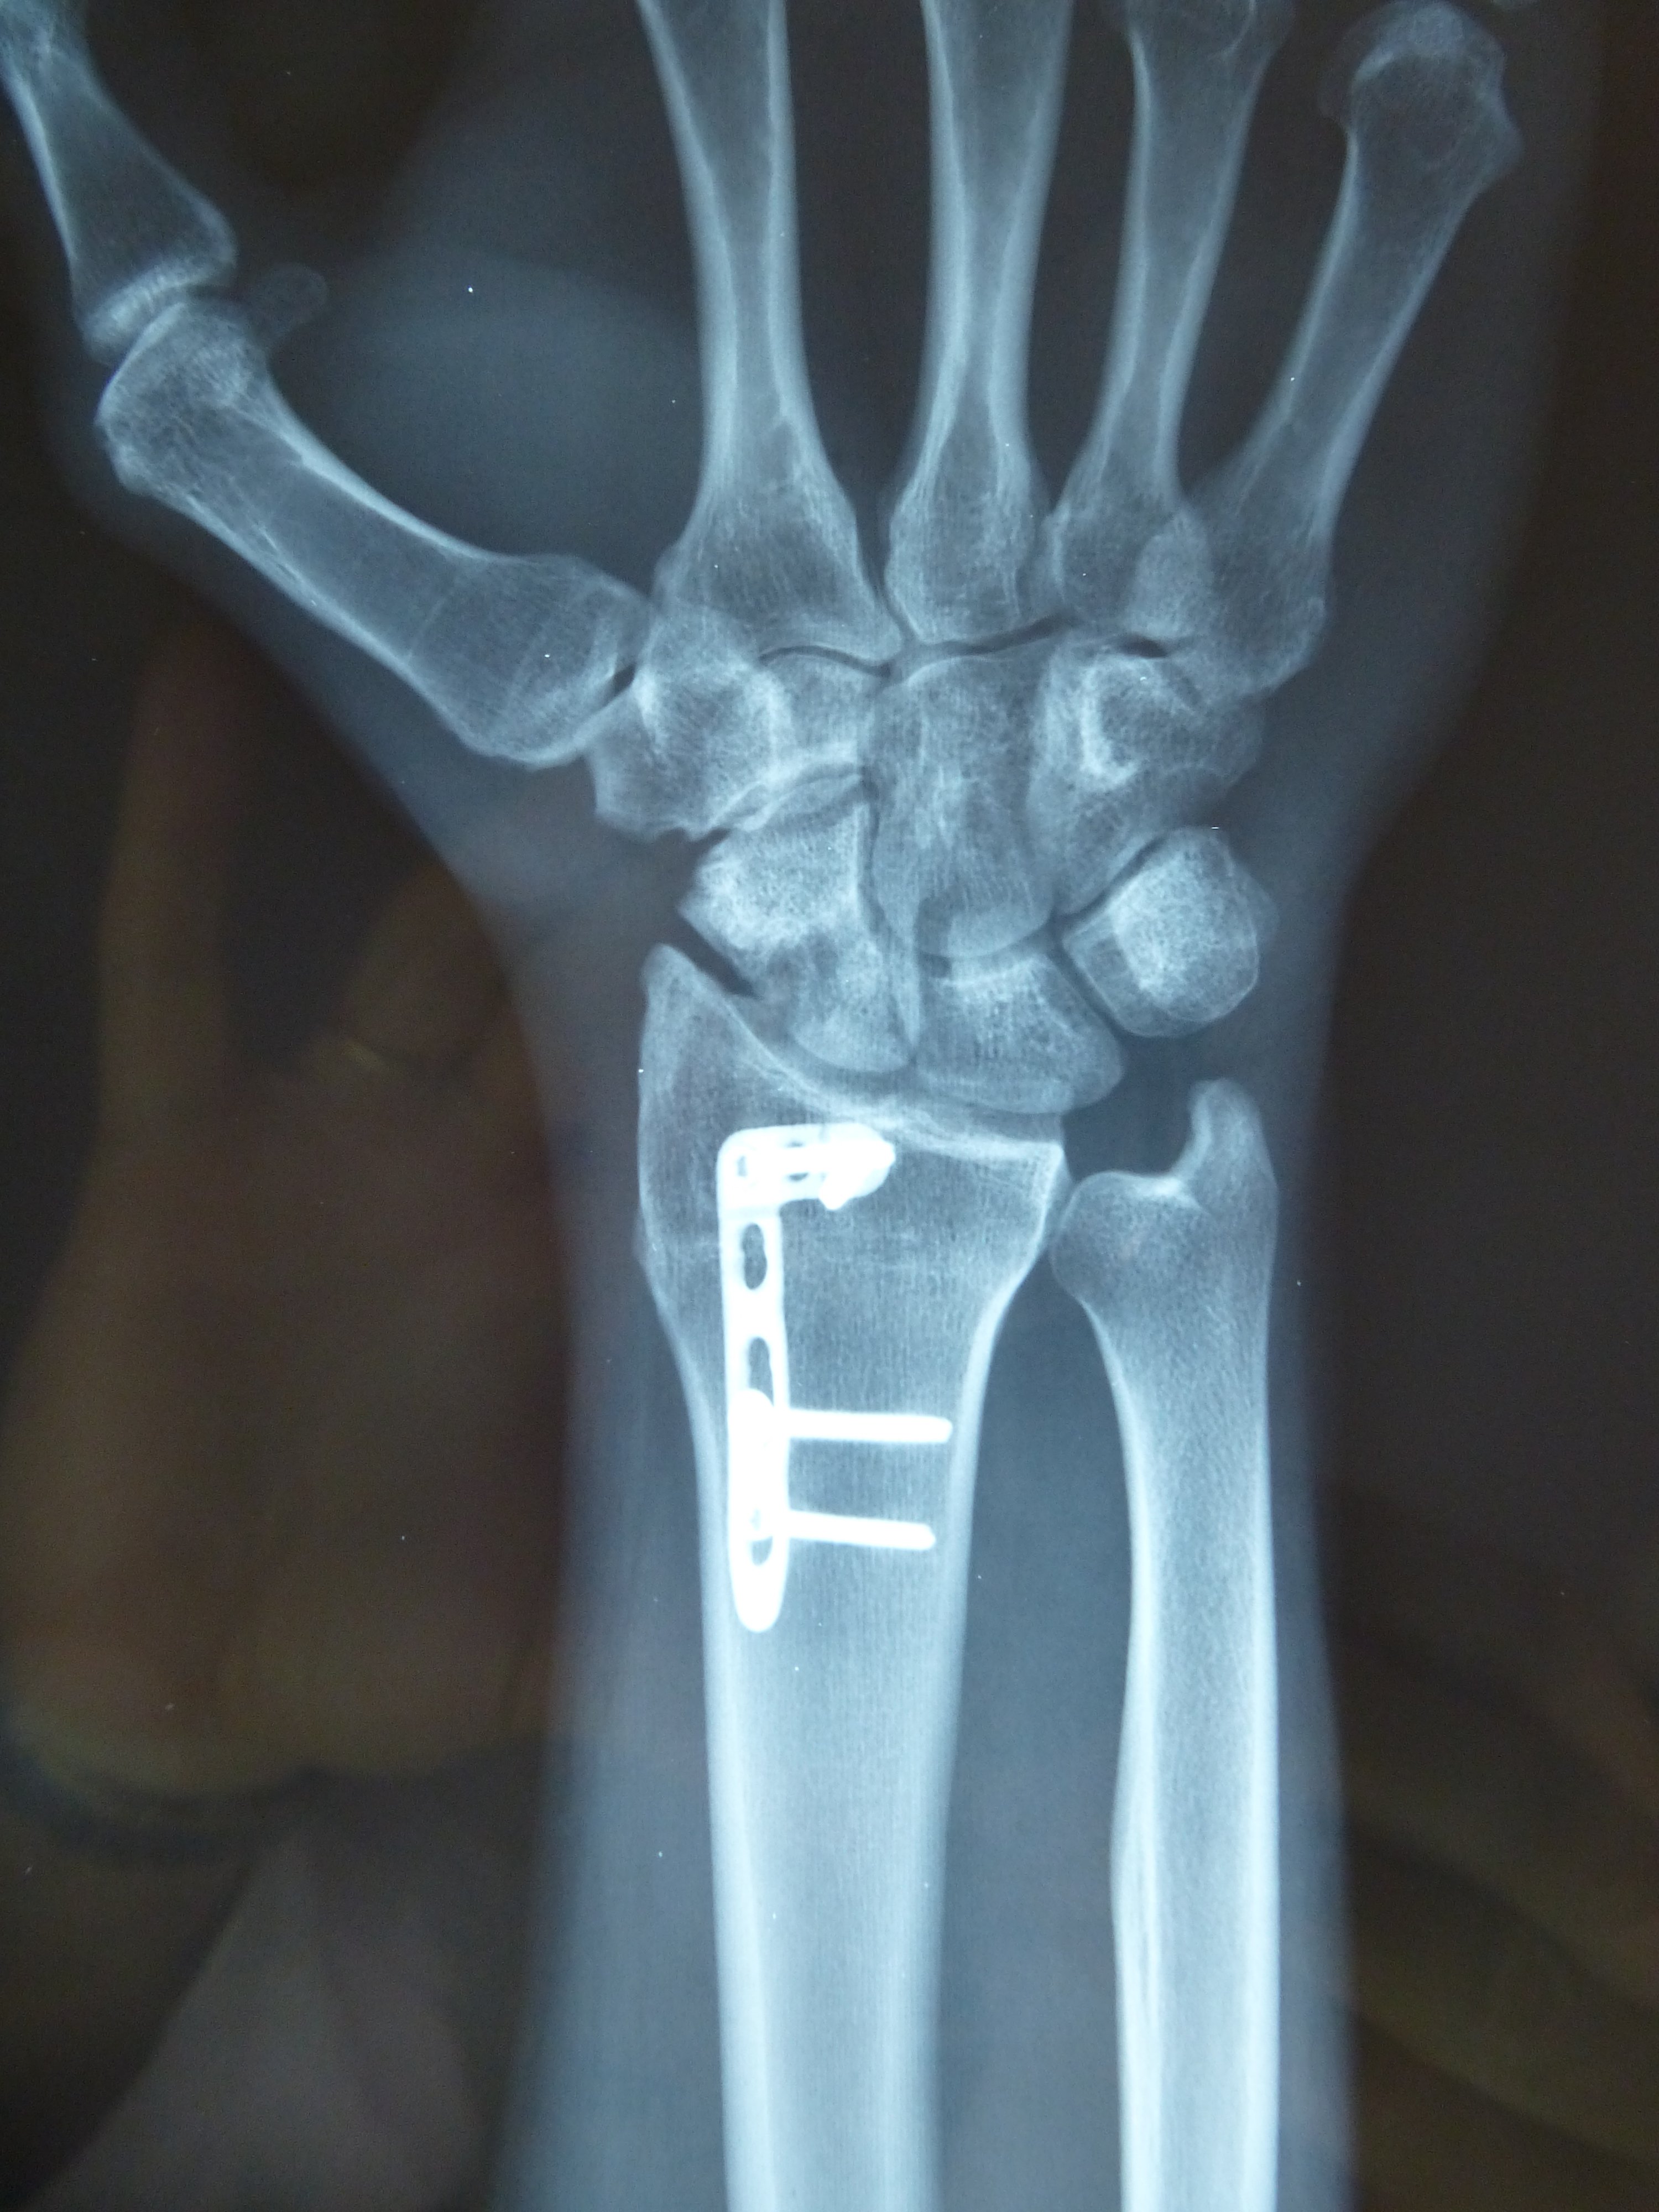

Η αντιμετώπιση της ψευδάρθρωσης του σκαφοειδούς είναι πάντοτε χειρουργική. Με ραχιαία ή παλαμιαία προσπέλαση αποκαθίσταται ο άξονας του σκαφοειδούς και σταθεροποιείται το σκαφοειδές με ειδική βίδα ή βελόνες, με παράλληλη τοποθέτηση οστικών μοσχευμάτων. Μπορεί επιπλέον να γίνει και οστεοτομία κλειστής σφήνας του περιφερικού άκρου της κερκίδος. Στις περιπτώσεις άσηπτης νέκρωσης το μόσχευμα πρέπει να είναι αγγειούμενο – για να προσδώσει αιμάτωση στο νεκρωμένο κεντρικό τμήμα – και λαμβάνεται με μικροχειρουργικές τεχνικές από το περιφερικό τμήμα της κερκίδος ή από άλλα τμήματα του σώματος

Μετεγχειρητικά 2

Περίπτωση 2: Μετεγχειρητικά 2